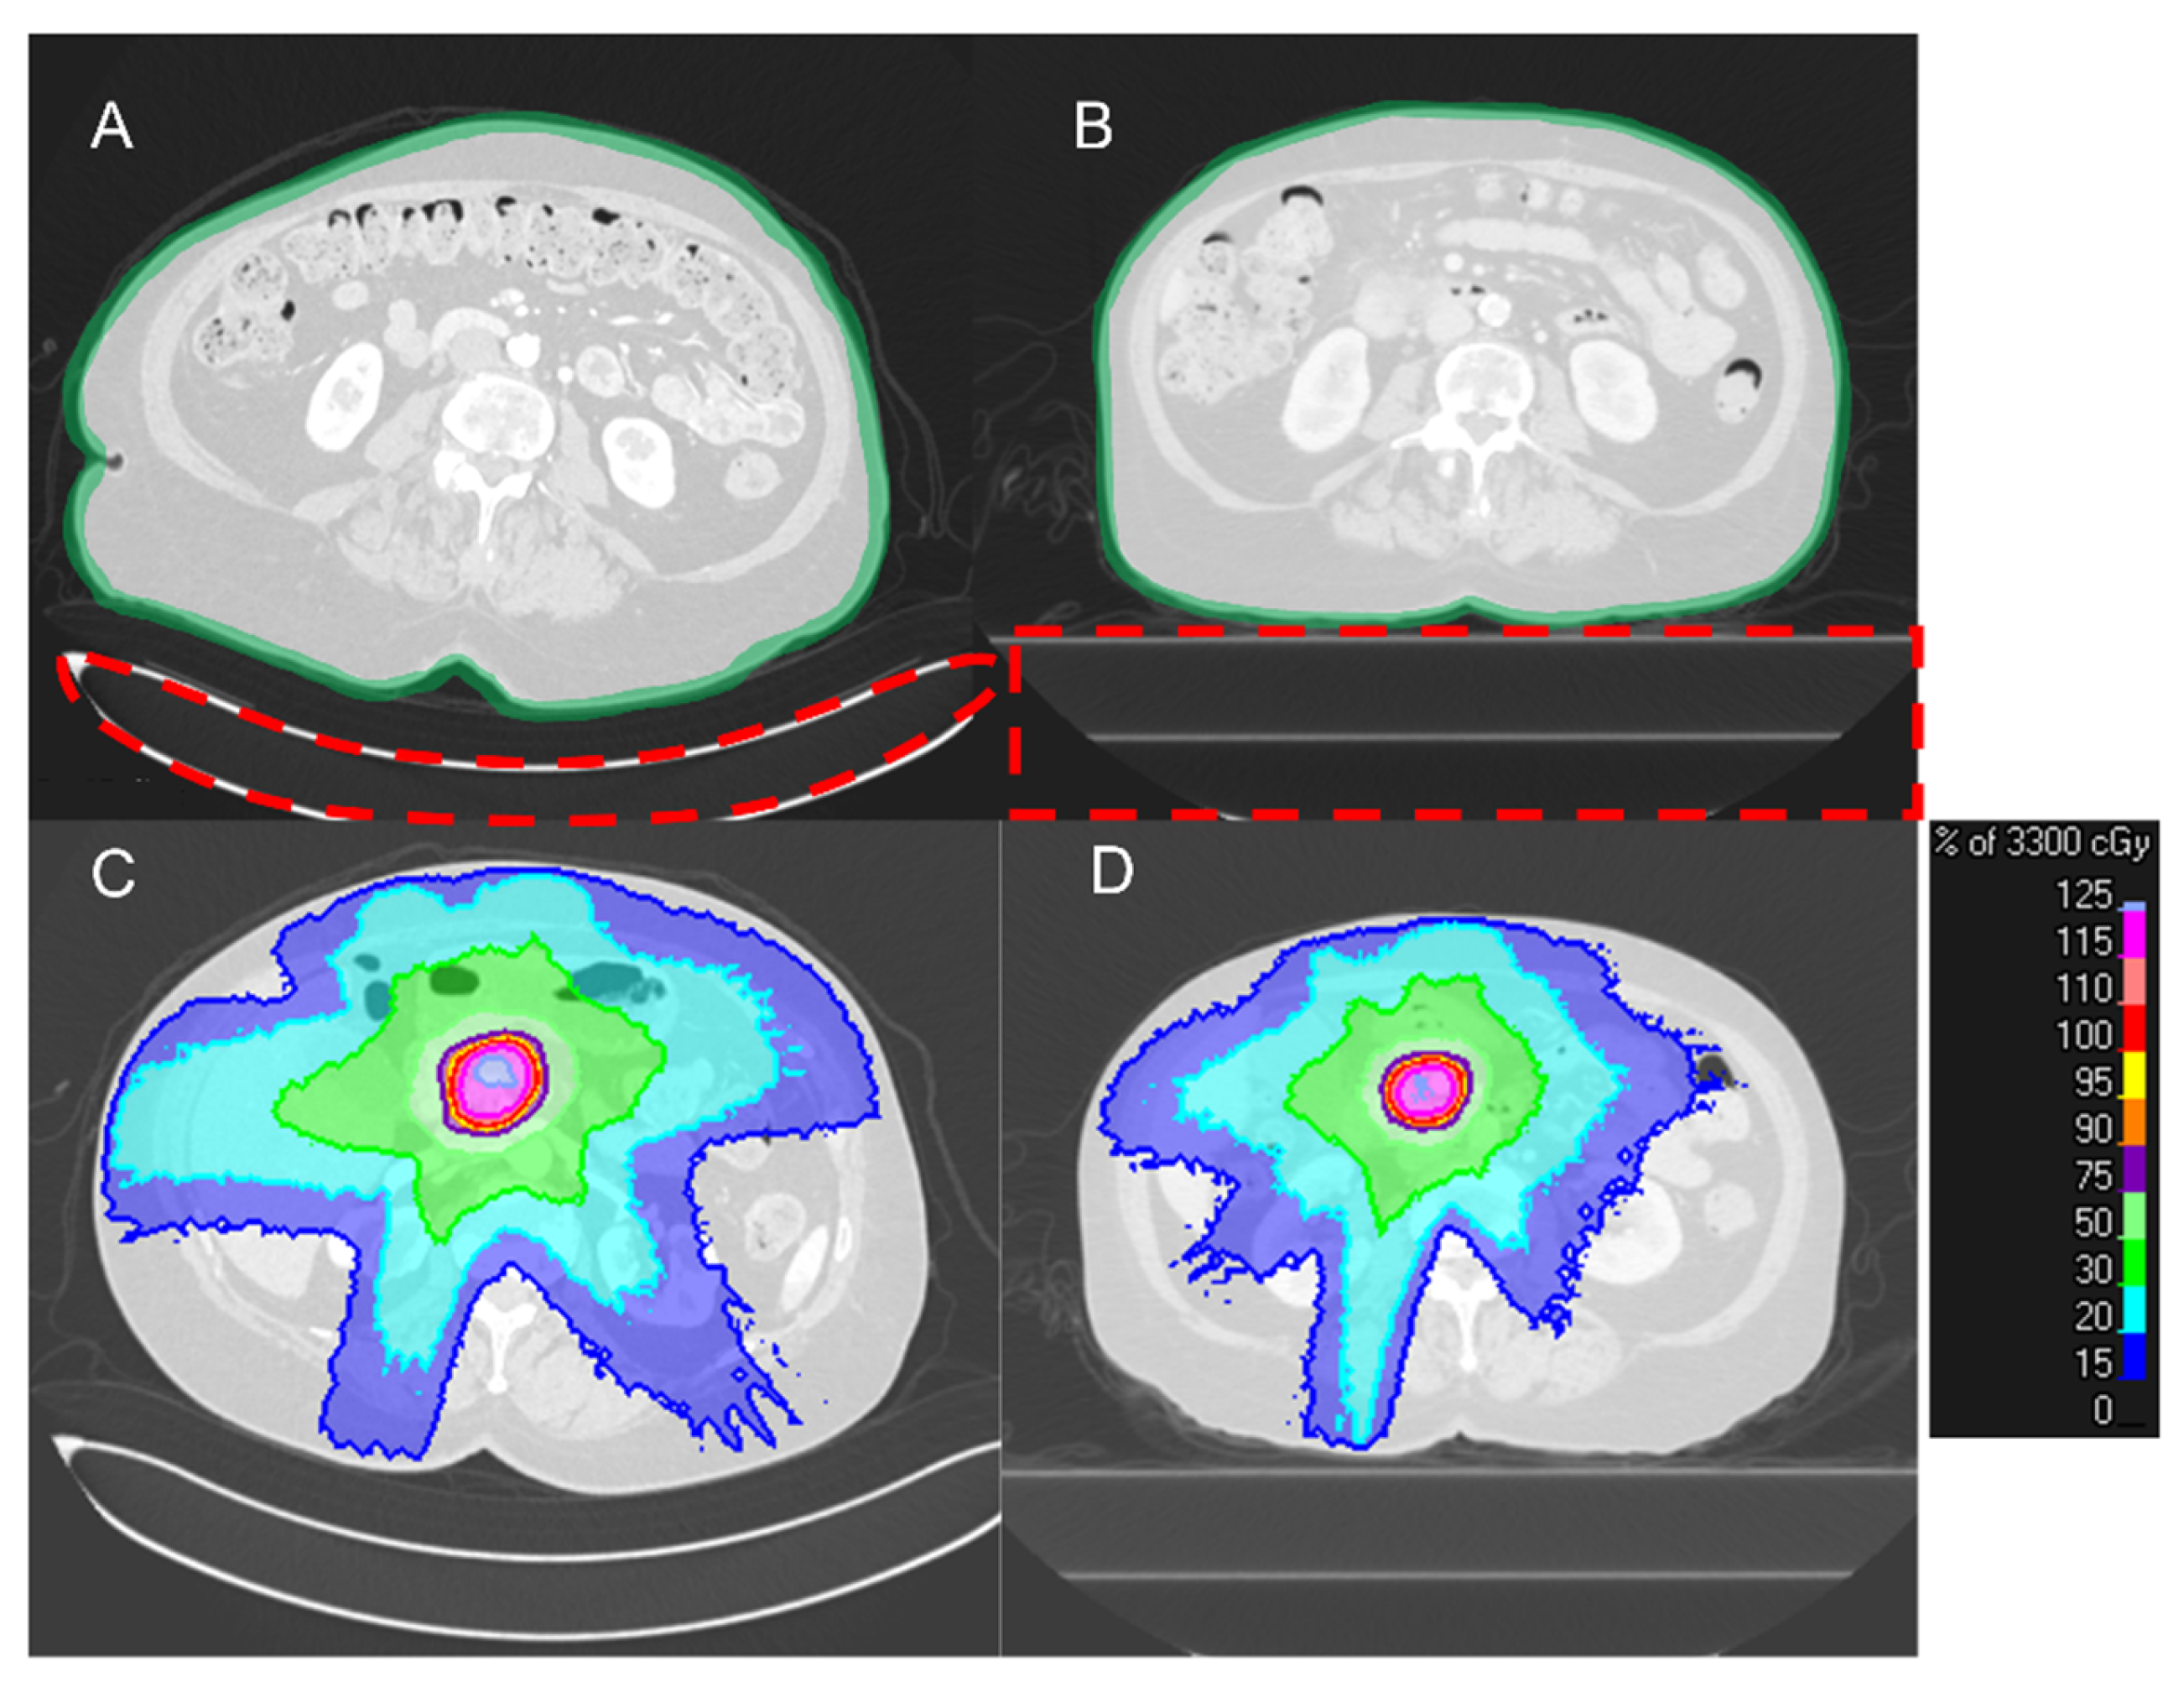

2.4. Radiation Therapy Planning

2.8. Placement of the Virtual Couch